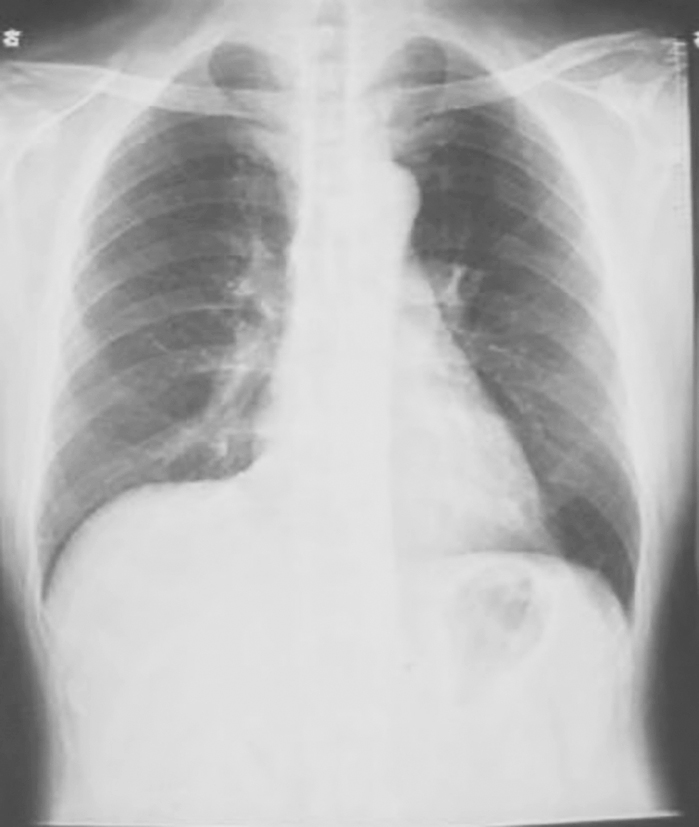

图2|X线胸片(2009-11-11)

X线胸片示左下叶斑片影较前明显吸收

图4|X线胸片表现(2009-11-17)

X线胸片示双肺多发结节影